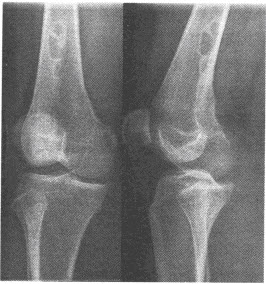

男,17岁,右腿酸痛、肿胀2个月余。右膝关节平片如下,最可能的诊断为()

A:纤维性骨皮质缺损

B:非骨化性纤维瘤

C:骨化性纤维瘤

D:骨样骨瘤

E:骨巨细胞瘤